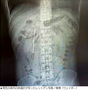

【写真】レントゲンに写った体温計

精密検査の結果、この物体は幼い時に飲み込んだ水銀体温計だったことが分かった。体温計は長期にわたり十二指腸に引っかかった状態が続いていたが、先端が腸の壁に触れているため穿孔(せんこう)や内出血を引き起こす恐れのある危険な状態だったという。

医療チームは内視鏡を使って約20分かけて体温計を取り出した。体温計は長期にわたり胆管近くにあったが、破損はなく水銀も漏れ出していなかった。ただし外の目盛りはほぼ消えてしまっていた。